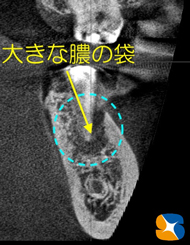

レントゲンCT画像分析の結果、動いているのはインプラントの1本手前のご自身の歯牙であることが判明しました。

上記は、おそらく根が割れているのでは?と思われるレントゲン画像です。

抜歯の結果、根は真っ二つ割れ、根の先端には大きな膿の腫瘍が骨を溶かしている良くない状態でした。

患者様は、迷わずインプラントを選択されました。抜歯と同時にインプラントの移植と自己血液を用いた骨の造成再生術を行われました。

腫瘍が骨を大きく溶かしていましたので、欠落した部分にCGFに人工の骨を混ぜ合わせ、骨の再生をインプラントの移植と同時に試みました。